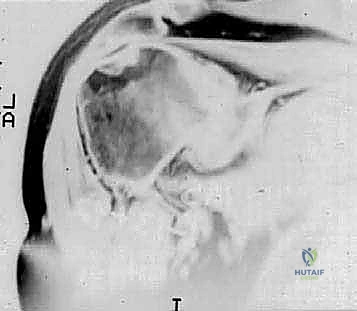

Glenohumeral arthritis is definitively a radiographic diagnosis, and standard imaging protocols are mandatory. A standard trauma series is insufficient; orthogonal views must include a true anteroposterior (Grashey) view in both internal and external rotation, and a high-quality axillary view. Radiographic hallmarks of primary osteoarthritis include profound subchondral sclerosis, expansive cyst formation, inferior humeral osteophytes, and asymmetric posterior joint space narrowing. The axillary view is absolutely critical for assessing the degree of posterior humeral head subluxation and the specific patterns of glenoid wear, which heavily influence surgical decision-making.

Computed Tomography (CT) scanning, preferably with advanced 3D reconstruction capabilities, is the current gold standard for quantifying glenoid version, assessing volumetric bone loss, and classifying the glenoid morphology according to the modified Walch classification system. Walch Type A represents a centered humeral head with concentric wear (A1 minor, A2 major central erosion). Type B denotes posterior subluxation (B1), posterior subluxation with biconcave posterior erosion (B2), or monoconcave posterior wear with severe retroversion (B3). Type C indicates profound glenoid hypoplasia with increased retroversion (>15 degrees) but without posterior subluxation. Type D represents anterior subluxation. Magnetic Resonance Imaging (MRI) is utilized selectively, primarily in patients with rheumatoid arthritis or those with clinical suspicion of a concomitant rotator cuff tear (e.g., profound weakness in external rotation or elevation), to confirm the structural integrity of the cuff prior to committing to an anatomic arthroplasty.

Clinical & Radiographic Imaging Archive